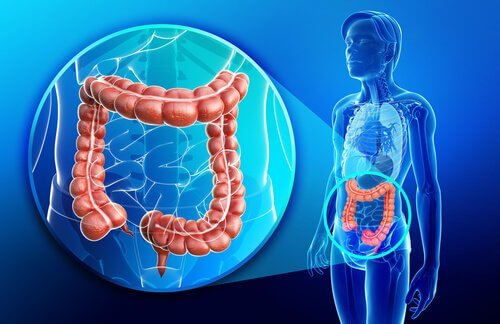

대장은 맹장, 결장, 직장 및 항문관을 포함하고 있다. 이들이 하나가 되어서 소화관에서 가장 넓지만 가장 짧은 부위가 형성된다. 오늘은 대장의 놀라운 생리학을 소개한다. 가장 먼저 신체의 중심부에 있는 대장은 수분과 전해질을 흡수하는 역할을 한다.

대장은 매일 약 1500 ml의 미즙을 받는다. 이는 주로 중심부에 위치한 결장에 있는 대부분의 수분과 전해질을 흡수한다. 그 결과 배출된 대변에는 약 100 ml의 수분과 1~5 mEq의 나트륨 및 염소 이온밖에 함유되어 있지 않다.